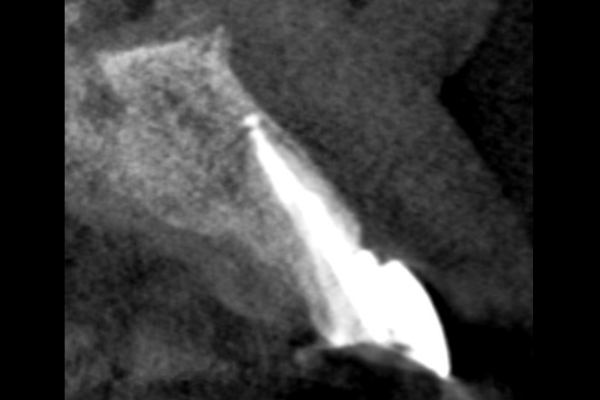

30代男性の小臼歯(奥歯)の症例

- 主訴

- 「奥歯で咬むと違和感がある」「時々歯茎が腫れる」とのことでご来院されました。数週間前から症状があり、他の医院では「抜歯の可能性がある」と言われ、不安に感じていらっしゃいました。

- 期間

- 治療期間2ヶ月、治療回数3回、レントゲン写真で治癒を確認できるまでの期間6ヶ月

- 治療内容

- 1.古い被せ物の除去と虫歯の徹底除去

まず、古い銀歯を外し、内部に広がっていた虫歯を丁寧に取り除きました。

2.マイクロスコープ下での根管治療

唾液などによる細菌の侵入を防ぐ「ラバーダム」を装着し、マイクロスコープ(歯科用顕微鏡)で根管内を数十倍に拡大しながら治療を進めました。複雑な形状の根管の内部まで、汚染された組織を徹底的に洗浄・消毒します。

3.根管充填(こんかんじゅうてん)

根管内が完全にクリーンになったことを確認し、再感染を防ぐために専用の薬剤で隙間なく密閉しました。

4.土台と被せ物の作製

歯の強度を補うための土台を立て、最終的なセラミックの被せ物を作製し、装着しました。

- 治療に伴うリスク

- 少しでも汚染物質が残ると再発のリスクが高まります。